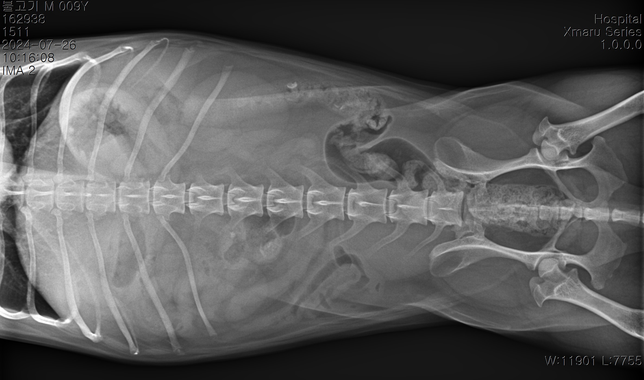

- 반려동물 건강반려동물Q. 순차적으로 고관절 에 관해 봐주시기 부탁드립니다.3 사진이 순차적입니다 순차적으로 고관절에 큰 변화가 있나요?마지막 보여지는 부분에서 오른쪽 고관절이 탈구된거라고 하는데 이전 사진에서는 탈구가 안되었나요?